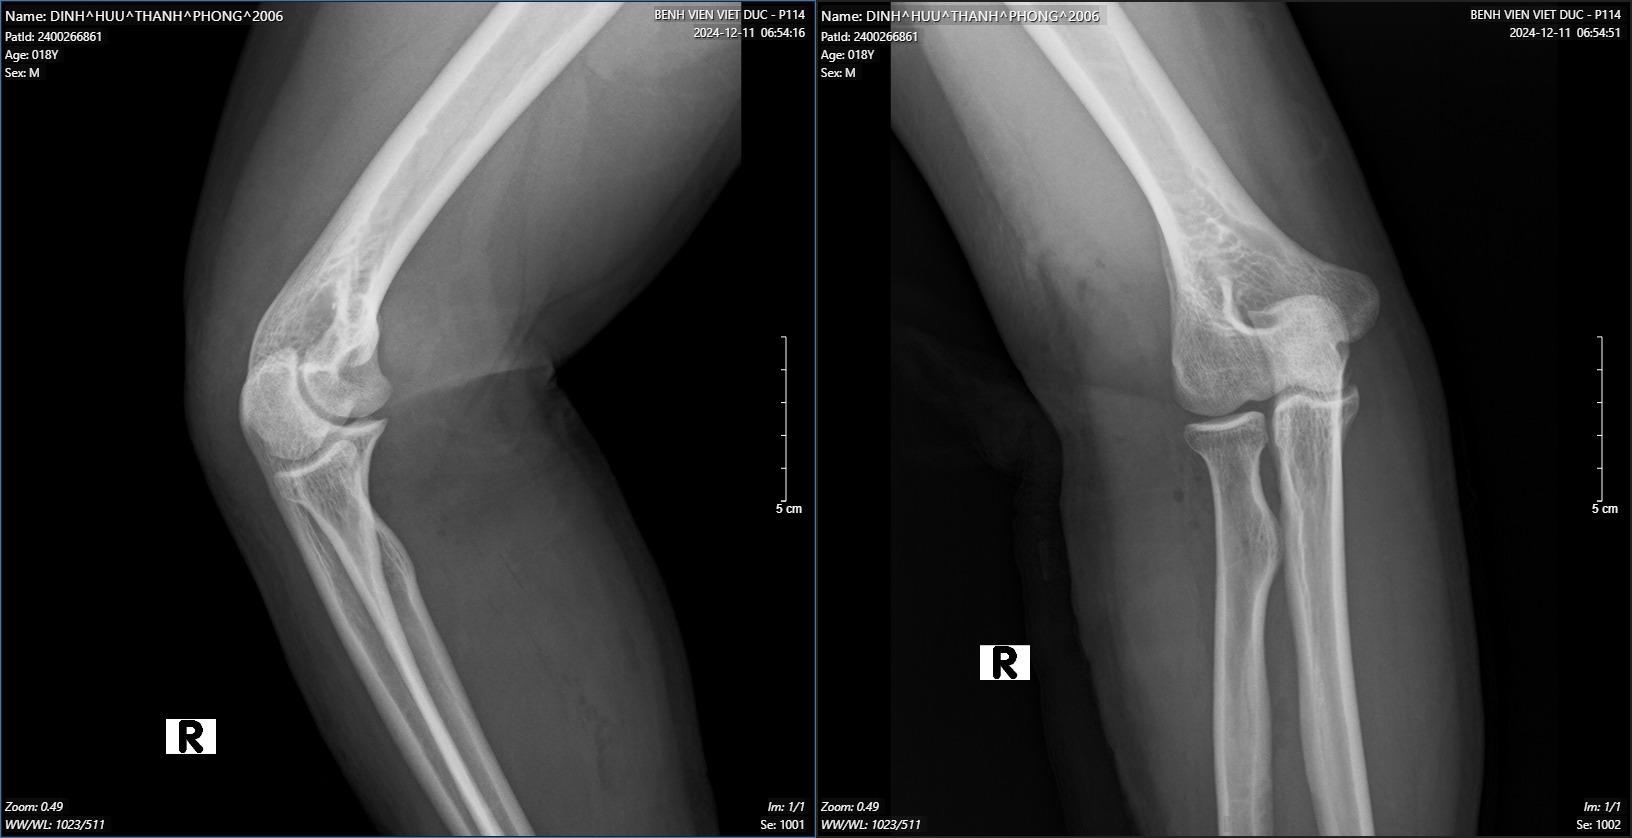

We present a case of an 18-year-old male patient, with a history of healthy development, no previous injuries in the elbow or forearm area. Five months before being admitted to the hospital, the patient began to experience progressively weakness in finger extension. Clinical examination showed the patient had normal shoulder joint movement, normal elbow extension, normal wrist extension, loss of extension and abduction of the thumb, loss of extension of the index, middle, and ring fingers, and weak extension of the little finger. On X-ray of the forearm, no bone lesions were noted, and MRI of the forearm showed no abnormalities. The patient was indicated for an upper limb nerve ultrasound, which showed a posterior interosseous nerve injury over a 25mm segment in the upper third of the forearm near the elbow. The segment of the nerve injury was noted to have an increased diameter, while the segments before and after the nerve injury were of normal size. The patient was diagnosed with posterior interosseous nerve entrapment syndrome and was indicated for nerve decompression surgery. The anterolateral approaching incision was 15 centimeters long, going between the brachioradialis and the extensor carpi radialis longus to access the radial nerve. During the surgery, we found that the patient’s posterior interosseous nerve was compressed by the Leash of Henry in the radial tunnel and primarily by the fibrous band of the supinator muscle at the Arcade of Frohse, where the interosseous nerve passes through the supinator to the posterior lateral side. The posterior interosseous nerve was completely decompressed at five locations, and the patient was discharged after one day with a follow-up appointment and a schedule for regular rehabilitation. After 4 months of surgery, the patient has partially regained the ability to extend their fingers.

On examination, we found that our patient had symptoms of low radial nerve palsy: loss of extension and abduction of the thumb, loss of extension of the index, middle, and ring fingers, weak extension of the little finger. Still he had normal wrist extension. To diagnose the patient, we performed routine X-rays of the forearm, forearm MRI, electromyography, and peripheral nerve ultrasound. Imaging tests help identify the cause of nerve compression, which then guides the treatment approach. Many authors worldwide have reported discovering nerve compression masses through direct examination and supported MRI imaging. Fitzgerald4 et al reported 5 cases of lipomas in the forearm compressing nerves, including 4 cases compressing the posterior interosseous nerve and 1 case of a large lipoma compressing both the superficial branch and the PIN of the radial nerve. Maldonado7 et al also reported 2 clinical cases of lipomas directly compressing the posterior interosseous nerve, one lipoma located at the proximal border of the supinator muscle, and the other at the distal border of the supinator muscle. Park3 reported another cause of posterior interosseous nerve compression being a ganglion cyst. The X-ray results of our patient showed no bone lesions, and the MRI also did not reveal the presence of a space-occupying mass. On the other hand, the results of the electromyography indicate a complete posterior interosseous nerve injury, and the nerve ultrasound shows a localized nerve injury segment of 25mm in the upper third of the forearm near the elbow, with a slight increase in the size of the injury segment, while the segments before and after the injury are of normal size. Based on the clinical and paraclinical examination information, we are leaning towards posterior interosseous nerve entrapment syndrome, primarily caused by compression at the “radial tunnel.”